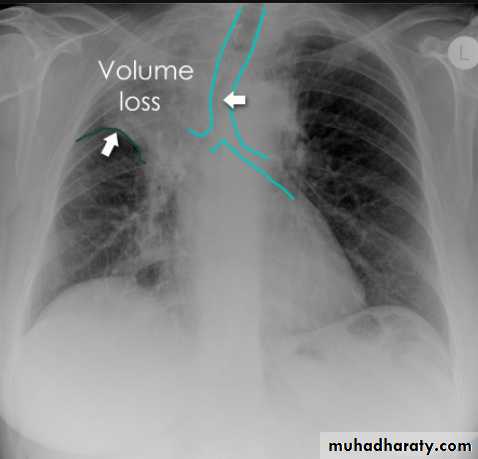

Some features, however, are generic markers of volume loss and are helpful in directing ones attention to the collapse, as well as enabling distinction from opacification of the lobe without collapse (e.g. lobar pneumonia). These features include 5:

elevation of the ipsilateral hemidiaphragm

crowding of the ipsilateral ribs

shift of the mediastinum towards the side of atelectasis

crowding of pulmonary vessels or air bronchograms